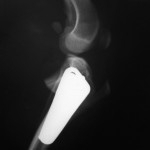

Kreuzbandriss Hund Kniegelenk TPLO Tibial Leveling Osteotomie nach Slocum Seitennaht lateral sutur Meniskus Meniskusschaden Tierarzt